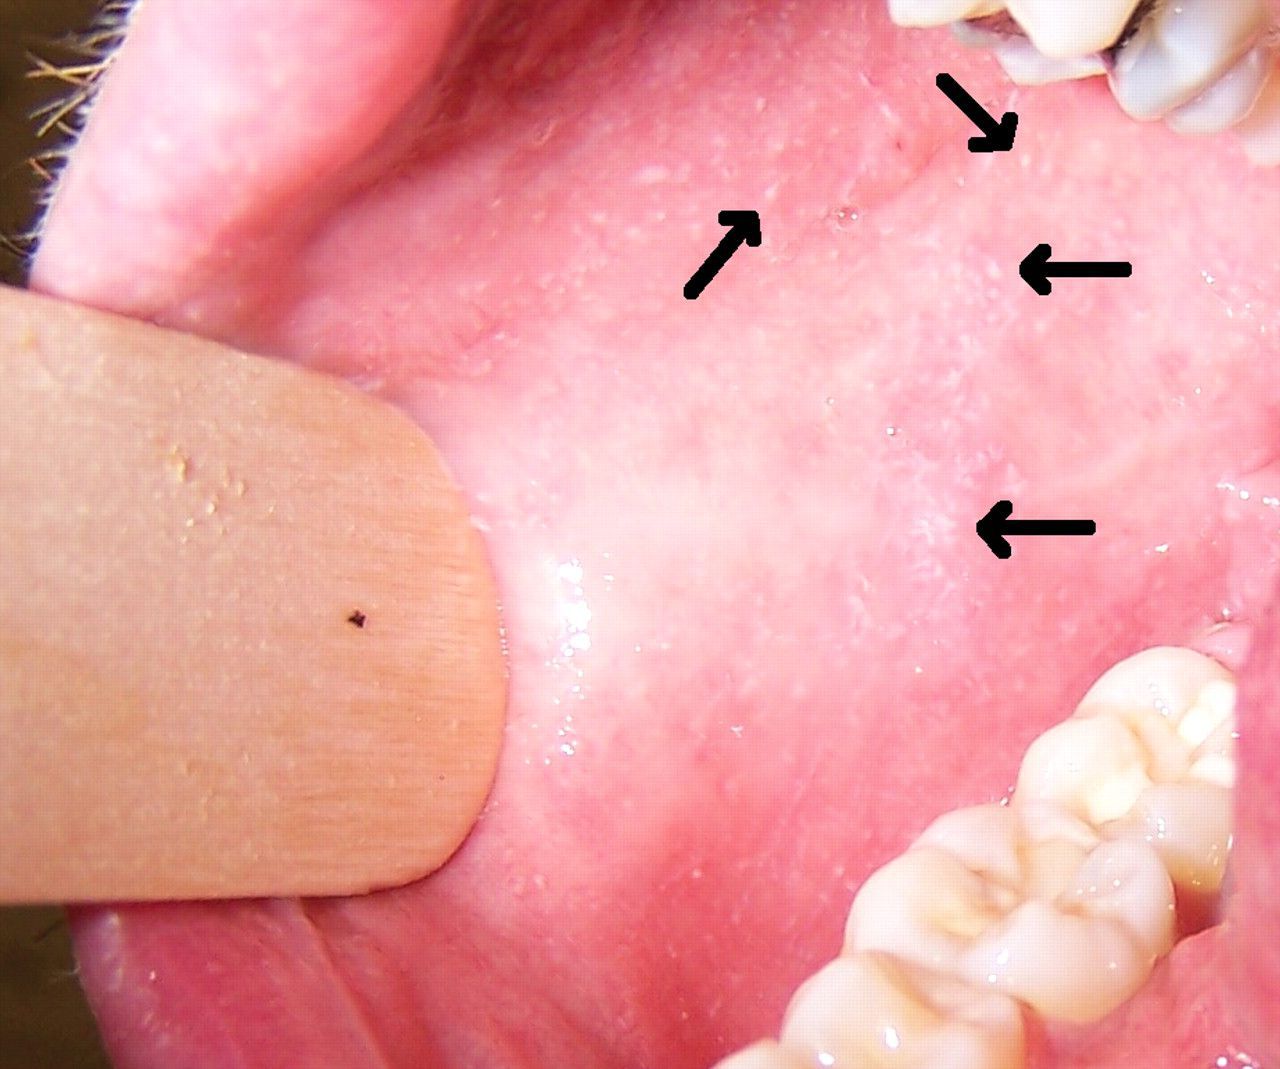

Koplik's spots (also Koplik's sign) are a classic sign of measles that occur two to three days before the measles rash itself appears. The characteristic features of these spots are that they are clustered, white lesions on the buccal mucosa. The other diagnostic signs of measles include 3 C:Cough, coryza and conjunctivitis.